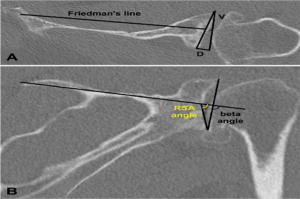

In a level III study, Tashjian et al. analyzed 168 RSAs with 13% of instability found the only risk factor significantly associated with instability was the superior inclination of the baseplate after controlling for age, sex, body mass index, and primary versus revision procedure (24). This fact emphasizes the importance of preoperative planning and meticulous placement of the baseplate. Inclination of the glenoid can be reliably measured on true anteroposterior radiographs of the shoulder joint using the beta-angle described by Maurer et al. (39). Given that the correct position of the baseplate occupies the inferior two thirds of the glenoid, recently Daggett et al. proposed a modification to this measurement called the “reverse shoulder angle” to avoid underestimation of glenoid inclination (40) (Figure 3). Although 15º of inferior tilt of the baseplate was demonstrated to be associated with decreased rates of glenoid loosening and failure (2,16), further studies are necessary to correlate baseplate inclination with instability risk.

Glenoid version in the axial plane can be measured by different methods: Friedman, vault and scapular body line (50) (Figure 3A). In a level III study, Rouleau et al. (50) concluded that the Friedman method is the most reliable measurement of glenoid version. However, the reference points necessary for the Friedman method may not be available when dealing with severe bone loss revision RSA, and the only method of version measurement available may be the scapula spine axis (44). In these cases the three-dimensional computed tomography may be helpful.

Hill and Norris (41) described a useful measurement of eccentric bone defects using axillary X-rays. It was adapted for use with CT scans, helping to determine the size of structural bone grafts necessary to fill in the eccentric uncontained glenoid defects (Figure 3A).

Glenoid inclination in the vertical plane is another important measurement when planning glenoid baseplate positioning. Inferior tilt greater than 15º was shown to correlate with early glenoid loosening and failure (2,16). Tashjian et al. reported increased rates of instability after RSA with increased beta-angle (24). Although glenoid inclination can be reliably measured using the beta angle (39,42), it can be underestimated when planning a RSA. Recently Daggett et al. proposed the “reverse shoulder angle” which seems to be more specific for RSA baseplate fixation (40) (Figure 3B).